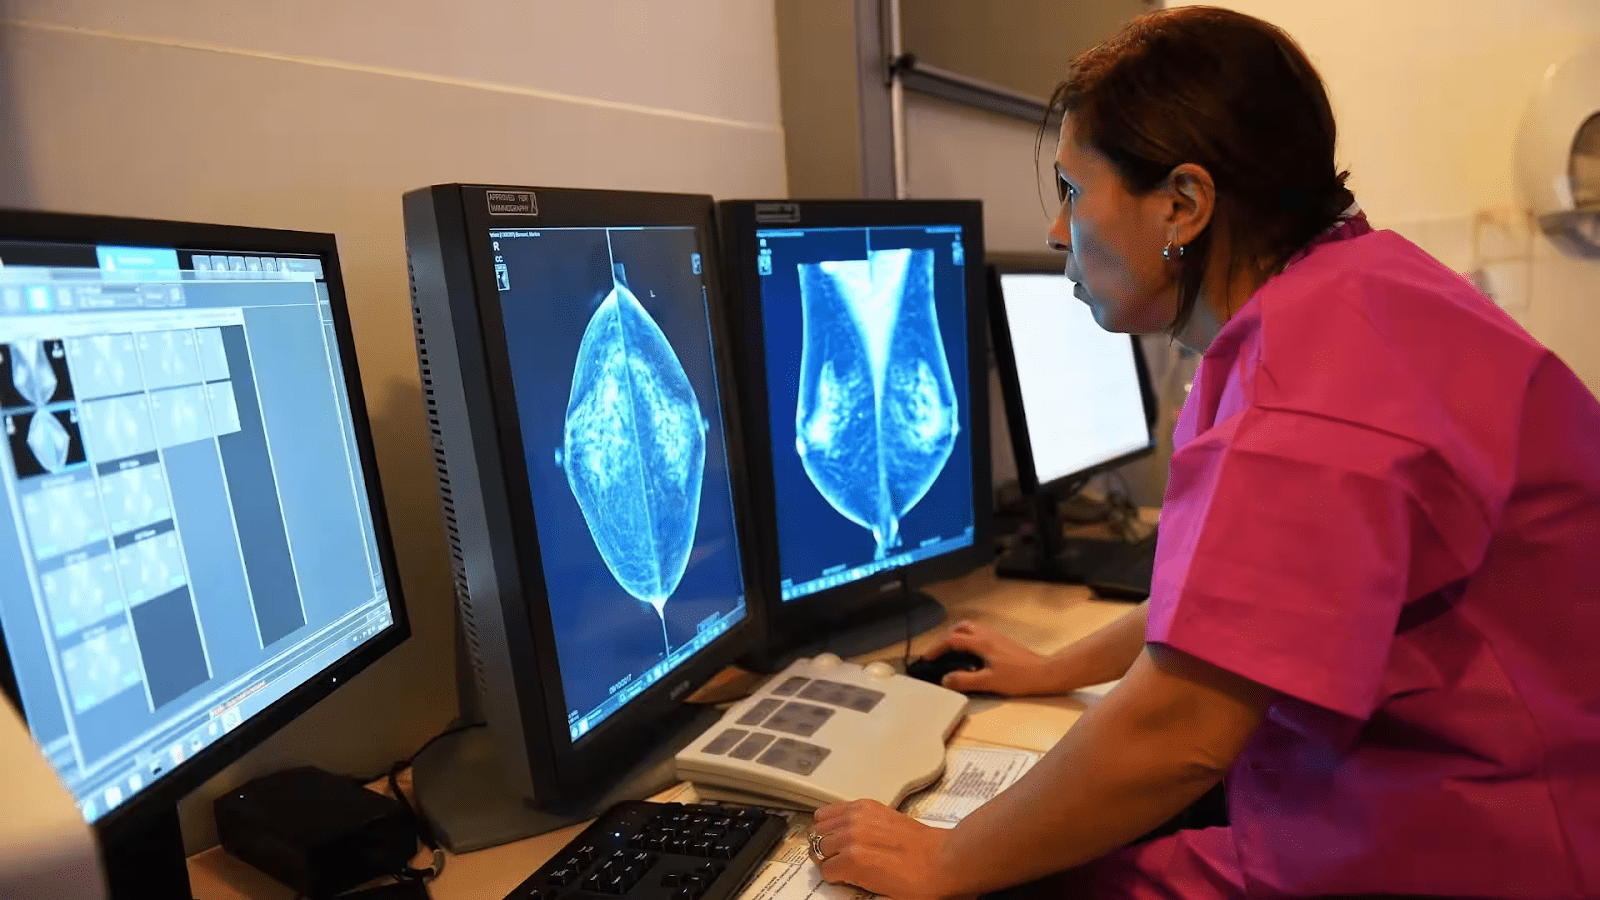

Жінка встає перед спеціальним рентгенівським апаратом. Технолог кладе груди на одну пластину, друга буде щільно притискати молочну залозу зверху. Пластини розплющують груди, утримуючи їх під час рентгенівського знімка. Людина протягом процедури може відчувати не дуже приємний тиск, але в цілому процес не має викликати сильного дискомфорту. Зазвичай роблять два знімки, аби лікар міг подивитися на груди збоку. Інша молочна залоза буде обстежена таким же способом. Потім жінка чекає в кабінеті, поки технолог перевірить рентгенівські знімки, щоб переконатися, що їх не потрібно переробляти. Також варто зазначити, що технолог не має права повідомляти про результати мамографії, це повинен зробити кваліфікований лікар.

Проходити мамографію для більшості дівчат незручно, деяким жінкам навіть боляче, проте це зазвичай пов’язано з проблемами зі здоров’ям. Однак, мамографія триває лише кілька хвилин, що не може не радувати пацієнток. Окрім цього, варто знати, що відчуття під час процедури залежать від кваліфікації технолога (у Ванкувері з цим проблем немає), розміру грудей і того, наскільки їх потрібно притиснути. До того ж, у когось молочні залозі більш чутливі, наприклад, якщо незабаром у жінки менструація. Лікар, який має спеціальну підготовку, називається радіологом, у Ванкувері він одразу перевірить рентгенівський знімок на наявність ранніх ознак раку молочної залози або інших проблем.